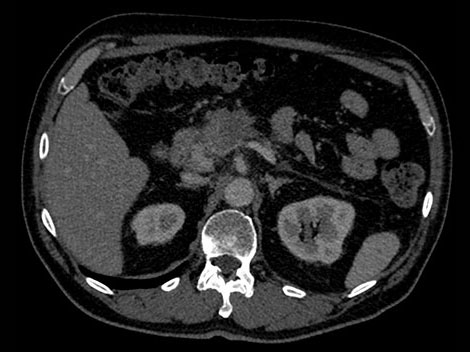

Wiek: 51 Wzrost: 183 cm" Masa ciała: 79 kg Skan CTA jamy brzusznej z 70-sekundowym opóźnieniem wstrzyknięcia środka kontrastowego

Wiek: 50 Wzrost: 180 cm" Masa ciała: 75 kg Skan CTA jamy brzusznej z 70-sekundowym opóźnieniem wstrzyknięcia środka kontrastowego

W celu ustalenia jednoznacznego rozpoznania w tym hipotetycznym przypadku radiolodzy potrzebują większej ilości informacji na temat guza widocznego w trzustce.

Jeśli obraz uzyskany tradycyjną techniką tomografii komputerowej nie daje jednoznacznych odpowiedzi, konieczne może być poddanie pacjenta dodatkowemu obrazowaniu.

W przeciwieństwie do tradycyjnych obrazów CT obrazy uzyskane z użyciem detektora spektralnego za każdym razem dostarczają pełnych danych spektralnych — bez konieczności jakichkolwiek niestandardowych przygotowań czy specjalnej konfiguracji. Daje to możliwość retrospektywnej analizy danych spektralnych na dowolnym obrazie i z użyciem szerokiej gamy narzędzi do wizualizacji danych spektralnych. Możliwe jest np. dostosowanie poziomu monoenergetycznego czy uzyskanie map efektywnej liczby atomowej (Z effective). Spójrz niżej, aby się przekonać.